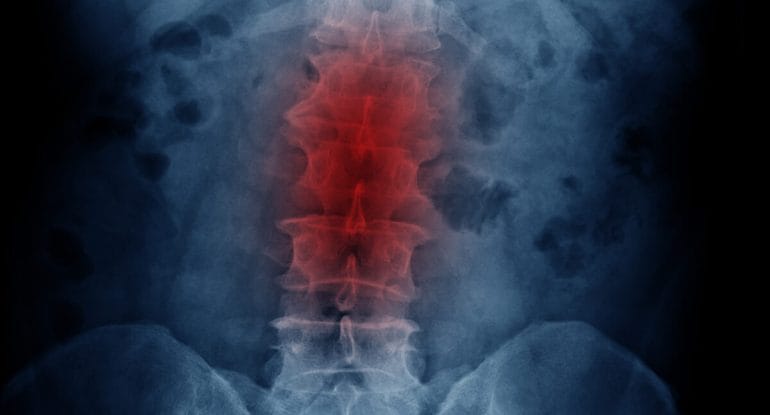

If DDD were simply caused by aging, then every disc in your spine would show equal degeneration. But that’s not what X-rays or MRIs show.

When reviewing X-rays with patients, I often show them two spinal joints:

- One joint with moderate or severe degeneration

- A joint directly above it that appears perfectly healthy

“These two joints were born on the exact same day. If degeneration were purely caused by age, both joints would look equally worn. But they don’t. That means something more than aging is at play.”